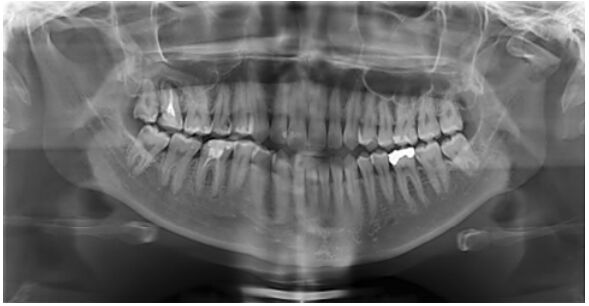

9.圖中所顯示的阻生齒,是屬於 Pell and Gregory 的那一種分類?

(A)class 2 B (B)class 2 C (C)class 3 B (D)class 3 C